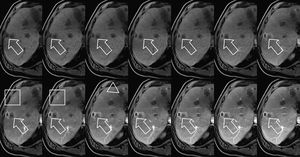

CAIPIRINHA-Dixon-TWIST (CDT) Volume-Interpolated Breath-Hold Examination (VIBE) is a new MR technique for fast Time-Resolved dynamic 3-Dimensional (3D) Imaging of the abdomen with high spatial resolution. The technique seems suitable for the detection and characterization of focal abdominal lesions such as liver and pancreatic masses. Figure: 73-year-old man who had previously undergone selective internal radiotherapy for colorectal cancer. There are large avascular metastases (arrowhead) in the left hepatic lobe and also an avidly enhancing subcapsular metastasis in segment 8 (arrow) exhibiting gradually increasing enhancement throughout the total acquisition. A second, only faintly enhancing metastasis can be appreciated anteriorly to the metastasis in segment 8 (box). Gradual filling of the distal portal vein branches is also noted (Michaely et al., 2013). #MRI #liver_imaging #liver_mr_imaging #CDT_VIBE